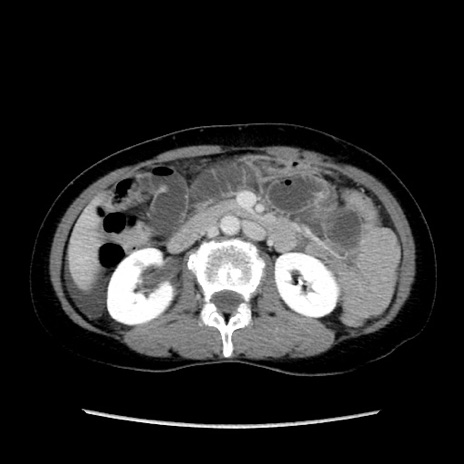

症例32(横断像)

【症例】40歳代 女性

【主訴】上腹部痛、嘔気・嘔吐

【現病歴】約9時間前頃から急に上腹部痛、嘔気、嘔吐が出現。改善しないため救急要請。

【既往歴】子宮頚癌(広汎子宮全摘術、放射線療法)、腸閉塞

【身体所見】腹部:平坦、軟、腸雑音亢進、上腹部を中心に腹部全体に圧痛あり。

【データ】WBC 8400、CRP 0.03